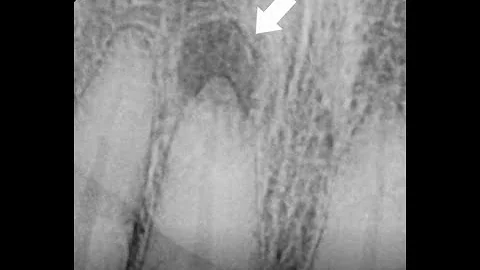

Why A Root Canal After A Crown - Sample Caesy Video

Why a Root Canal After a Crown? Crowns After Root Canal Therapy helps explain why a root canal is needed after a crown has ...